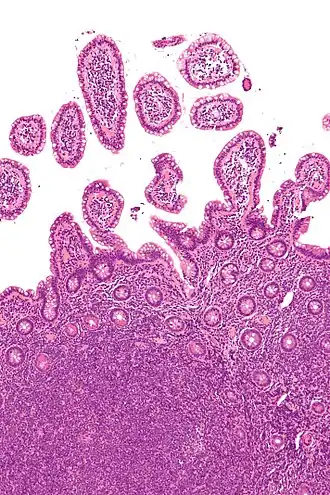

Biopsie de l'iléon terminal montrant au microscope un lymphome à cellules du manteau (coloration H & E).